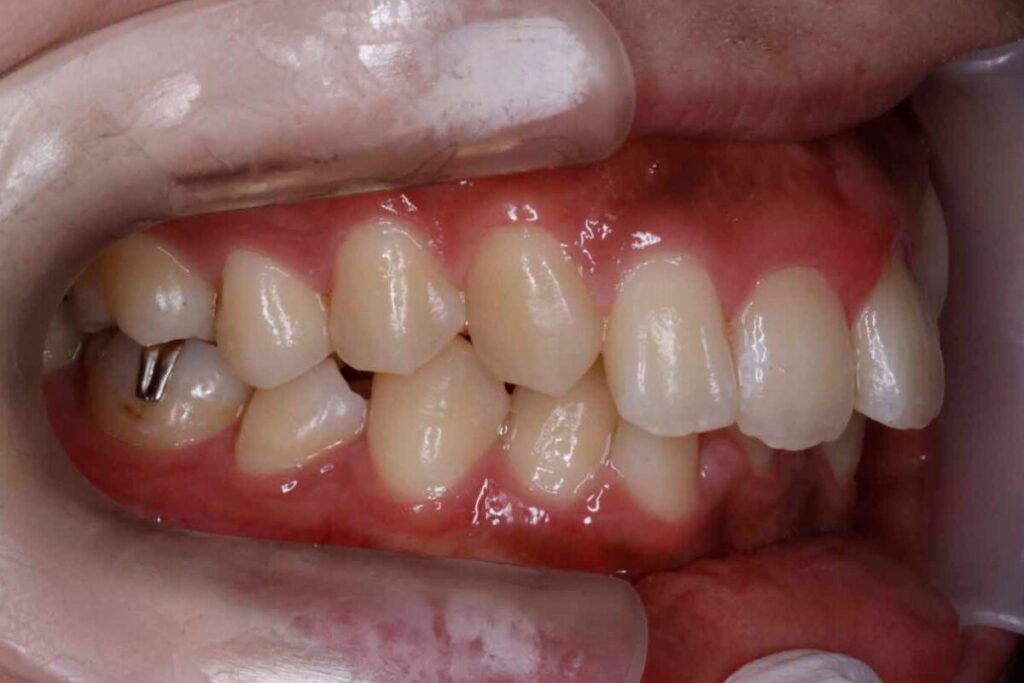

30代男性|過蓋咬合・叢生を非抜歯+インビザラインで改善(1年・783,750円)

噛み合わせの深さと歯並びのデコボコ感を気にされて来院されました。

診断では、叢生を伴う過蓋咬合と判断。咬合の深さを改善しながら歯列の並びを整えるため、非抜歯でのマウスピース矯正を選択しました。前歯の被蓋を浅くすることで、顎の動きや発音のしやすさも向上。

1年という短期間で、見た目の印象と機能のバランスが取れた咬合へと導くことができました。深いかみ合わせでも丁寧な設計でマウスピースでもしっかりと治せます。